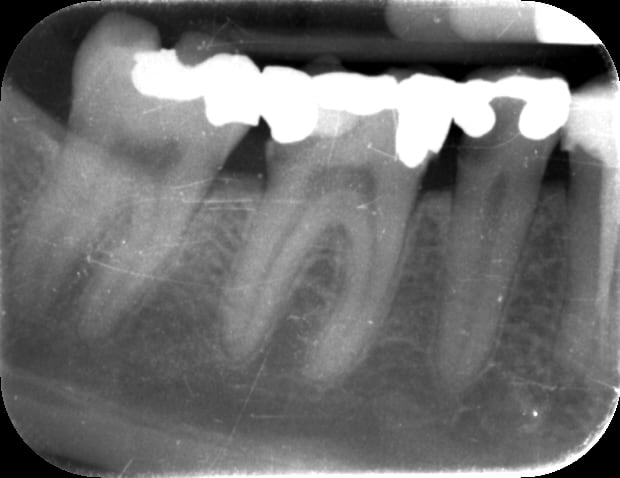

Onlay rxpréop yrf29j - Eugenol

Onlay rxp xfrksk - Eugenol

sur cette RX, effectivement, la pulpe a l'air de te donner plus de marge;)